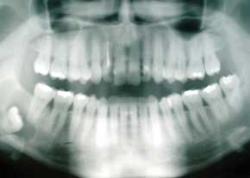

خطر راديوگرافي دندان

راديوگرافي‌هاي دندان براي مشخص كردن دندان‌هاي شكسته، استخوان‌هاي آسيب‌ديده، پوسيدگي، آبسه‌هاي دنداني ، كيست‌ها ، بررسي مفصل، بررسي رابطه استخوان‌ها و خيلي موارد ديگر كاربرد دارد. ممكن است تهيه راديوگرافي‌هاي دهان و دندان براي برخي از افراد نگران‌كننده باشد.

جام جم آنلاين: راديوگرافي‌هاي دندان براي مشخص كردن دندان‌هاي شكسته، استخوان‌هاي آسيب‌ديده، پوسيدگي، آبسه‌هاي دنداني ، كيست‌ها ، بررسي مفصل، بررسي رابطه استخوان‌ها و خيلي موارد ديگر كاربرد دارد. ممكن است تهيه راديوگرافي‌هاي دهان و دندان براي برخي از افراد نگران‌كننده باشد.

نوع ديگر راديوگرافي‌هايي است كه عمدتا براي بررسي پوسيدگي دنداني است كه به آنها راديوگرافي بايت وينگ گفته مي‌شود. گروه بعدي عكس‌هايي هستند كه براي بررسي تمام دندان‌ها يا بررسي استخوان‌هاي سر و صورت تهيه مي‌شوند كه در درمان‌هاي تخصصي‌تر مثل ارتودنسي استفاده مي‌شوند و هر كدام از اين منابع اشعه متفاوتي را به افراد مي‌رساند.